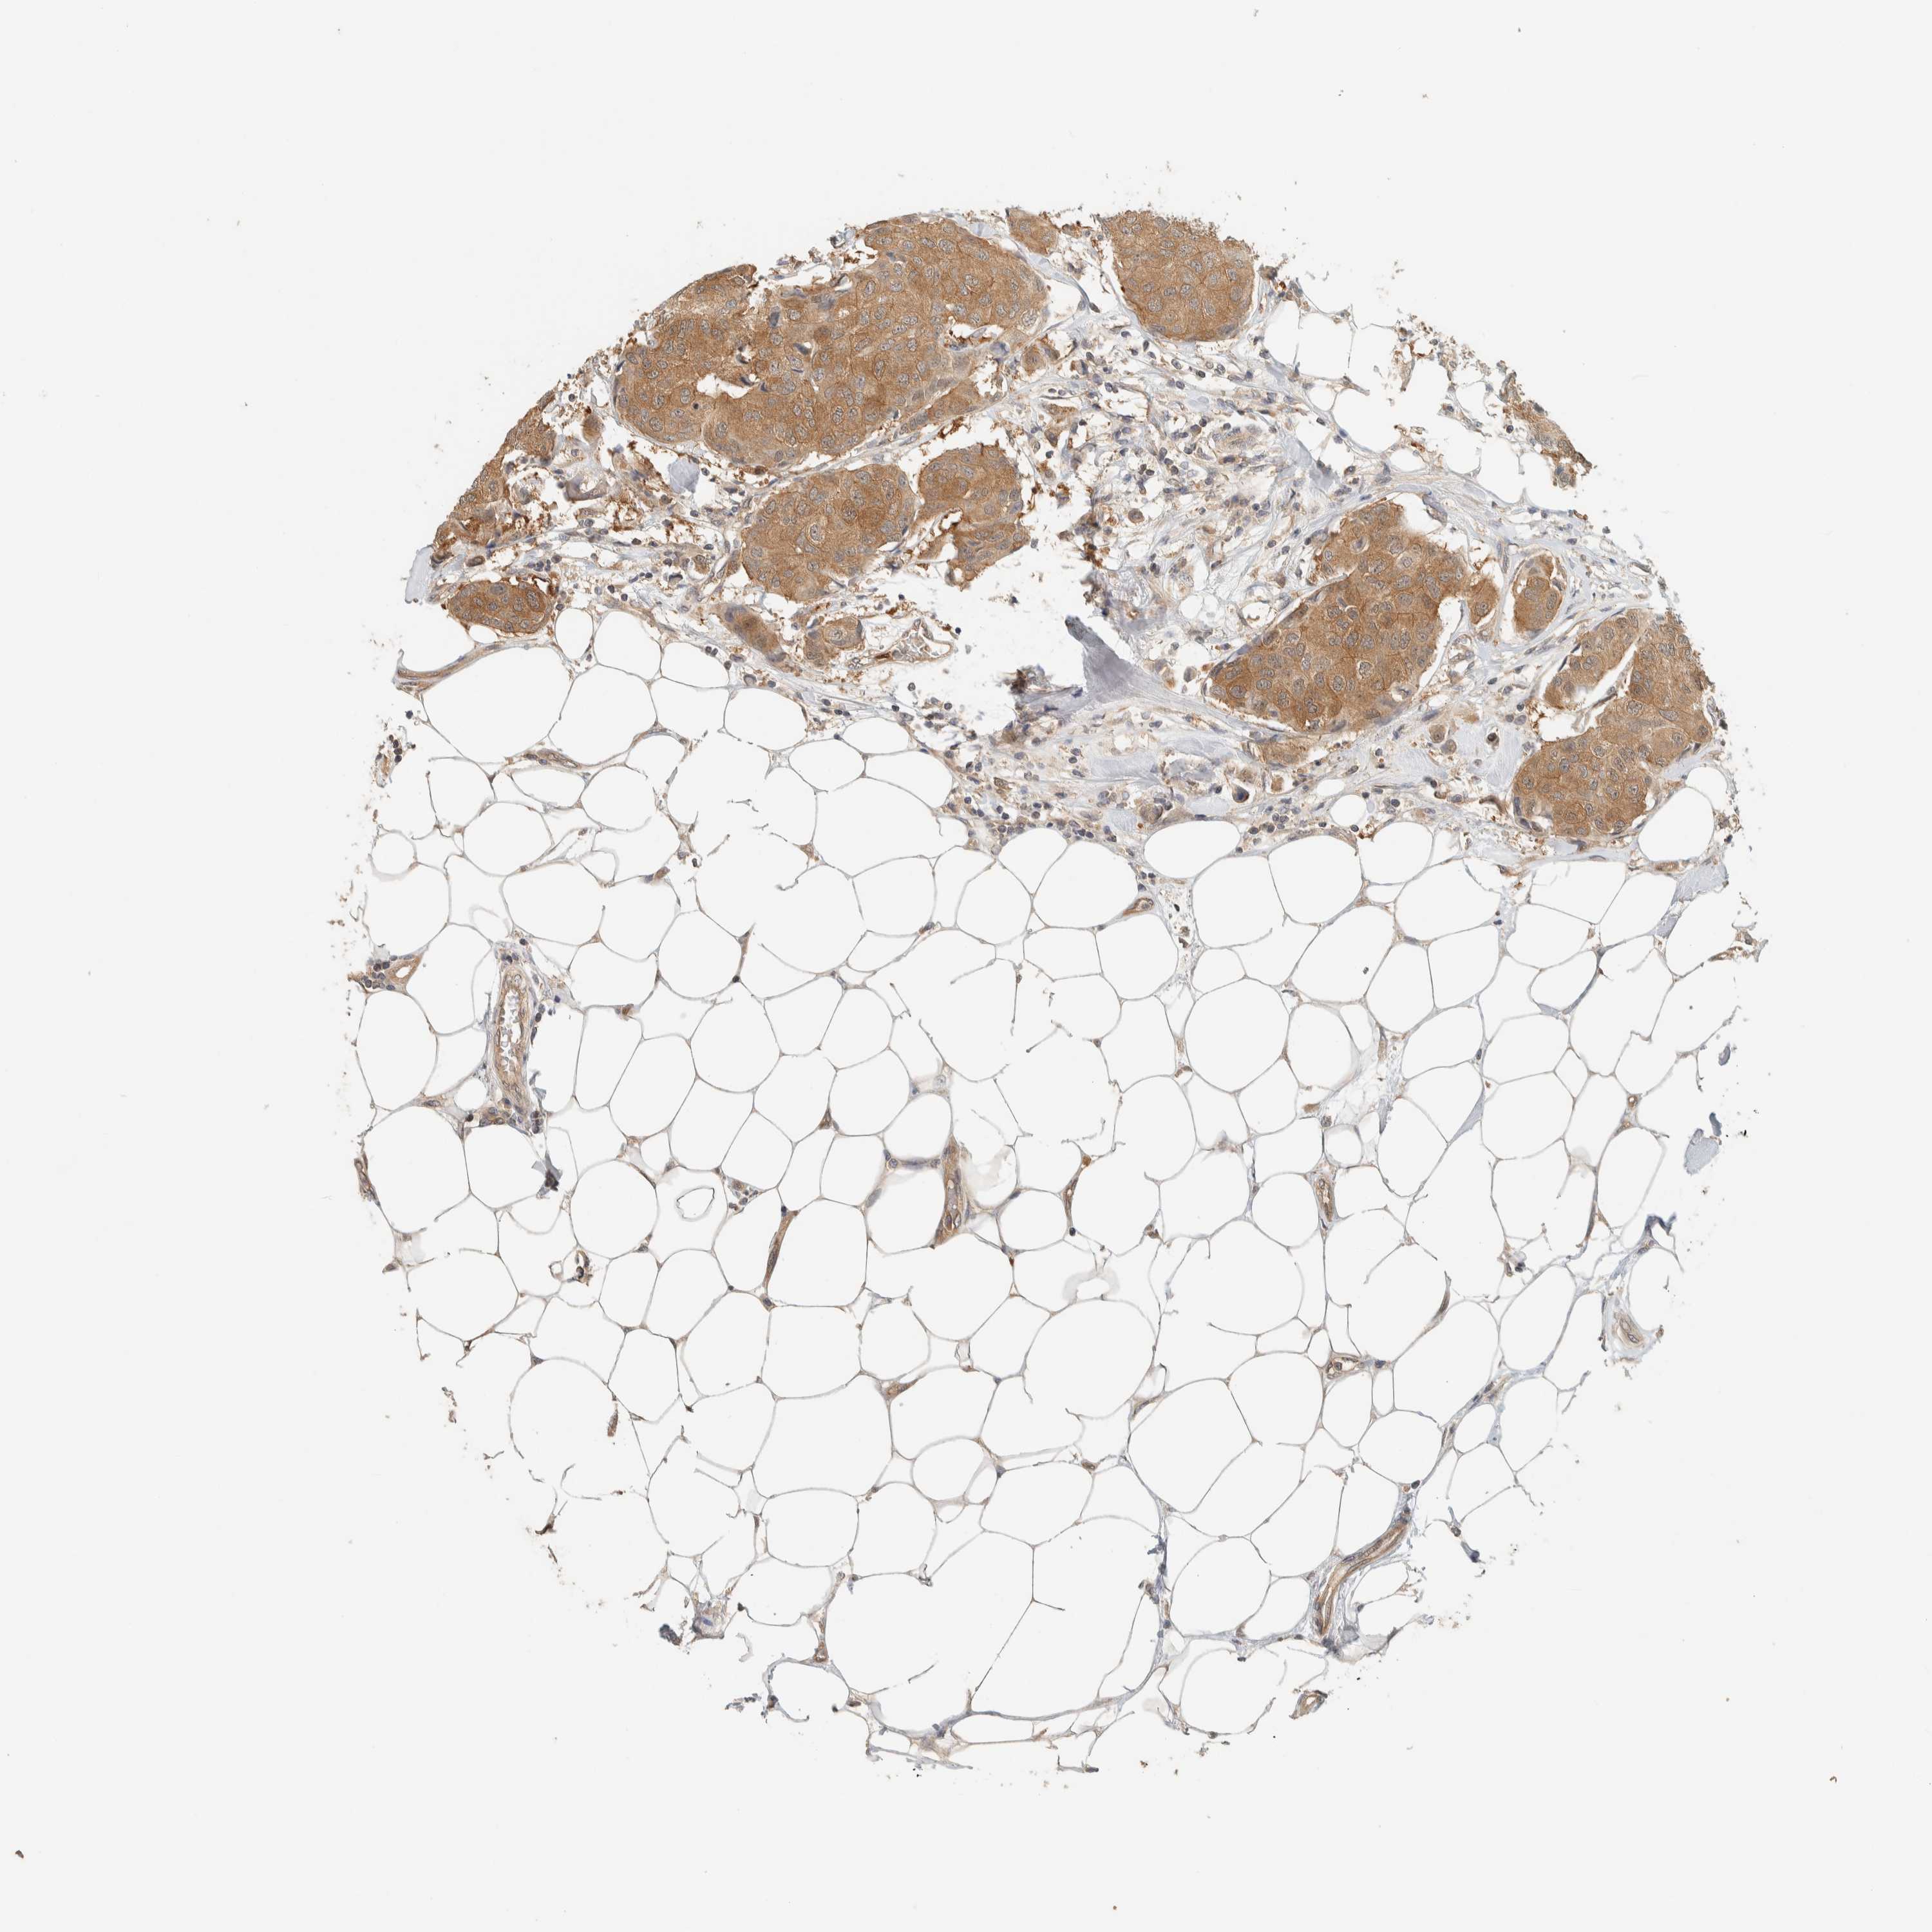

BRCA TCGA BRCA VALIDATION PROTEIN EXPRESSION